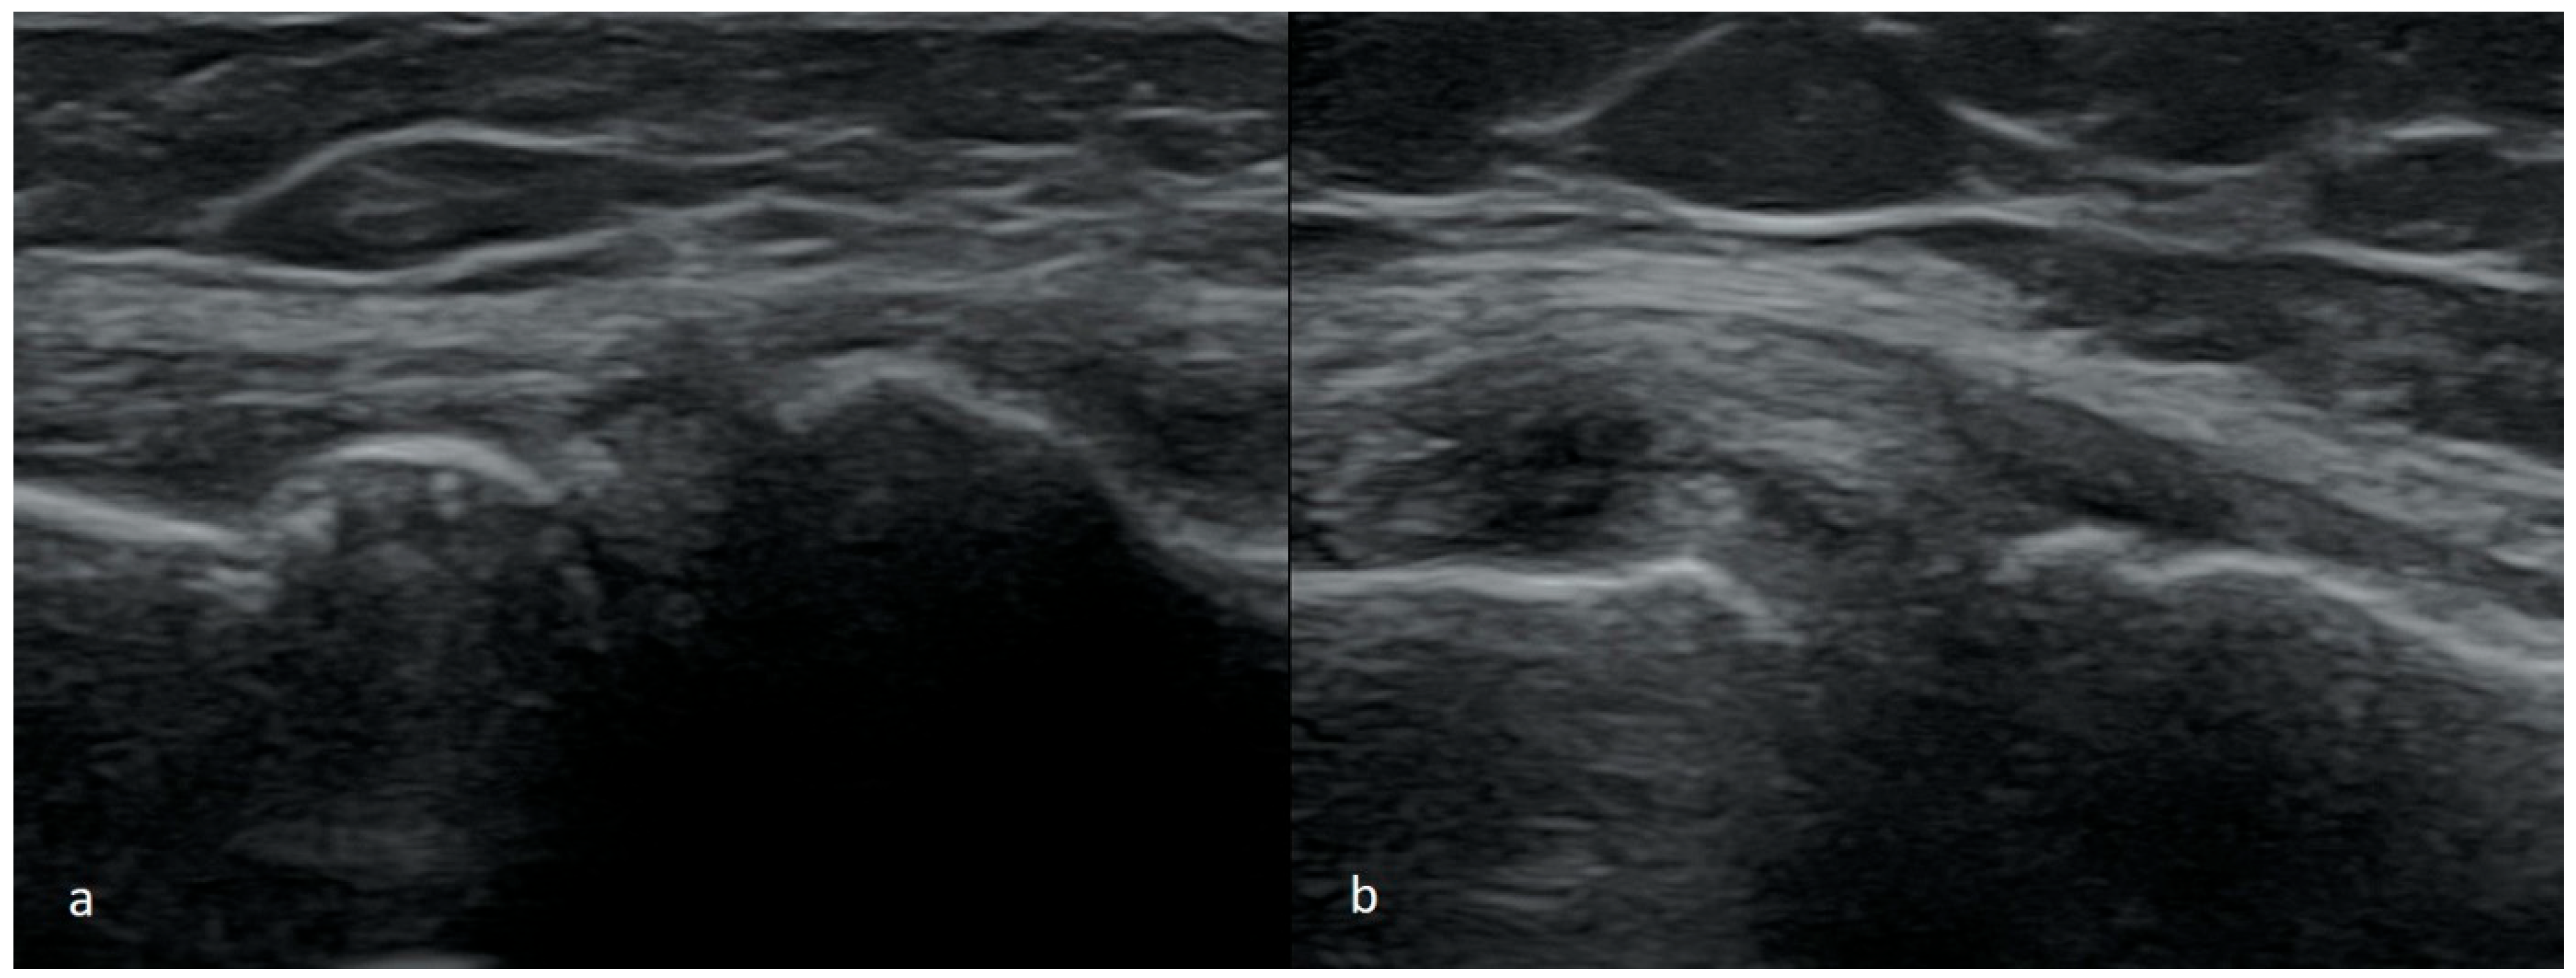

3.1.1. Meniscus Tears

3.1.5. Degenerative Changes of Menisci